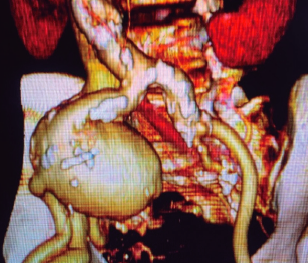

Los aneurismas aislados de arteria iliaca común son una patología infrecuente y habitualmente el diagnóstico es incidental. Su presentación clínica se caracteriza por los efectos compresivos del aneurisma sobre los tejidos adyacentes. Su ruptura a pesar de ser inusual tiene una tasa de mortalidad significativa. El manejo solía ser por vía abierta, pero con el advenimiento de la cirugía endovascular, se han identificado mejores desenlaces en los pacientes llevados a este tipo de procedimientos, reservando la reparación abierta en los casos agudos y rupturas. La asociación de aneurismas de iliaca a fistulas arteriovenosas ilio-ilíaca, llevados a reparación endovascular, se ha reportado únicamente en un solo caso a través de la búsqueda exhaustiva por diversas bases de datos. En el presente, se presentará un caso de un paciente masculino de 82 años, con esta asociación, en el cual se decidió llevar de manera electiva a manejo endovascular de su patología.